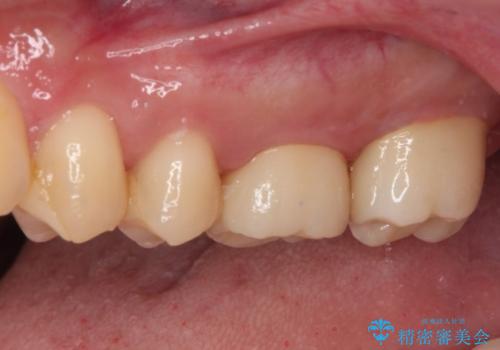

根管治療後、病変が消退したことを確認し、オールセラミッククラウンにて補綴治療を行うこととしました。

2,3回の処置後には来院時に感じていた痛みはなくなり、根管治療から半年後にはレントゲンでの根尖部病変も消失していました。